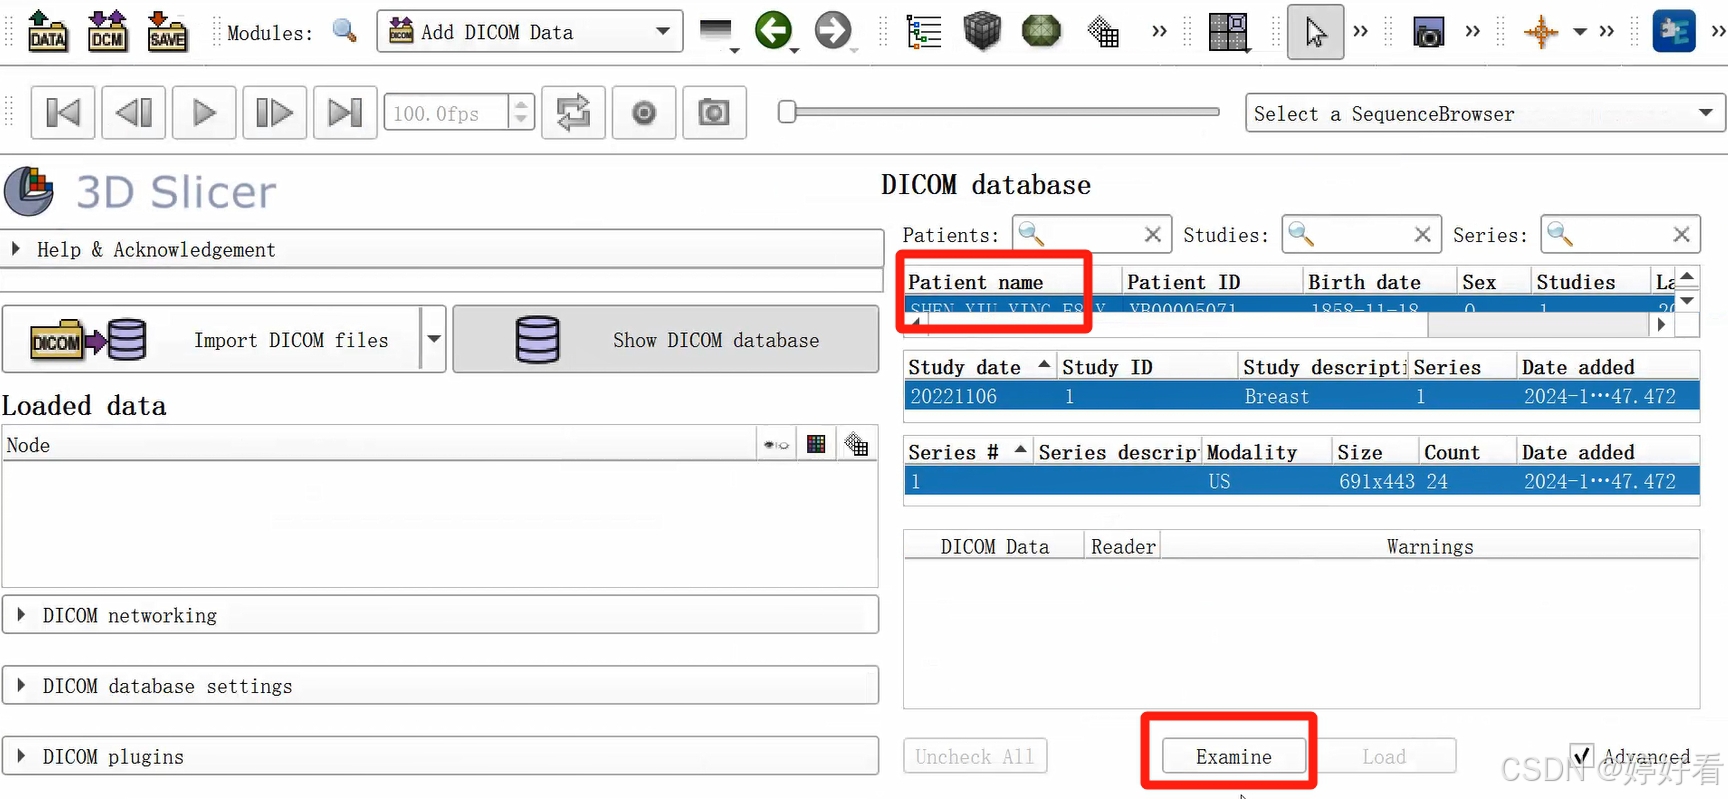

1.2 选中Patient name,然后依次点击Examine-Load,这样图片就打开了。